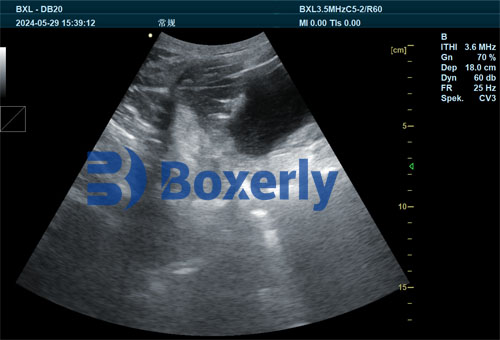

B-mode ultrasound generates two-dimensional grayscale images in real time. When the probe is placed on the sow’s abdomen or inserted transabdominally in the inguinal region, it emits high-frequency sound waves into the body. These waves reflect off tissues of differing densities—such as the uterus, amniotic fluid, and fetuses—and return to the probe, where they are processed into visual images.

Key structures that can be seen during pregnancy include:

Anechoic (black) fluid areas within the uterus, representing amniotic fluid

Hyperechoic (white) dots or lines representing fetal bones

Movement of the fetus as pregnancy progresses